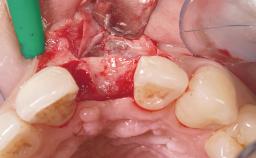

Late Placement of an Implant in a Maxillary Left Central Incisor Site

Soft Tissue Grafting Simultaneous

Abutment Type Customized

Prosthesis Type FDP